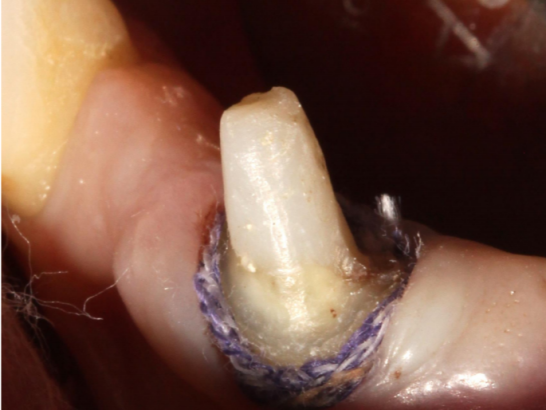

Case ii

Step 4: Place the second retraction cord in the gingival sulcus

Choose a retraction cord that fills the gingival sulcus. It can be observed that the retraction cord completely surrounds the tooth. The second retraction cord often needs to be impregnated with hemostatic material.